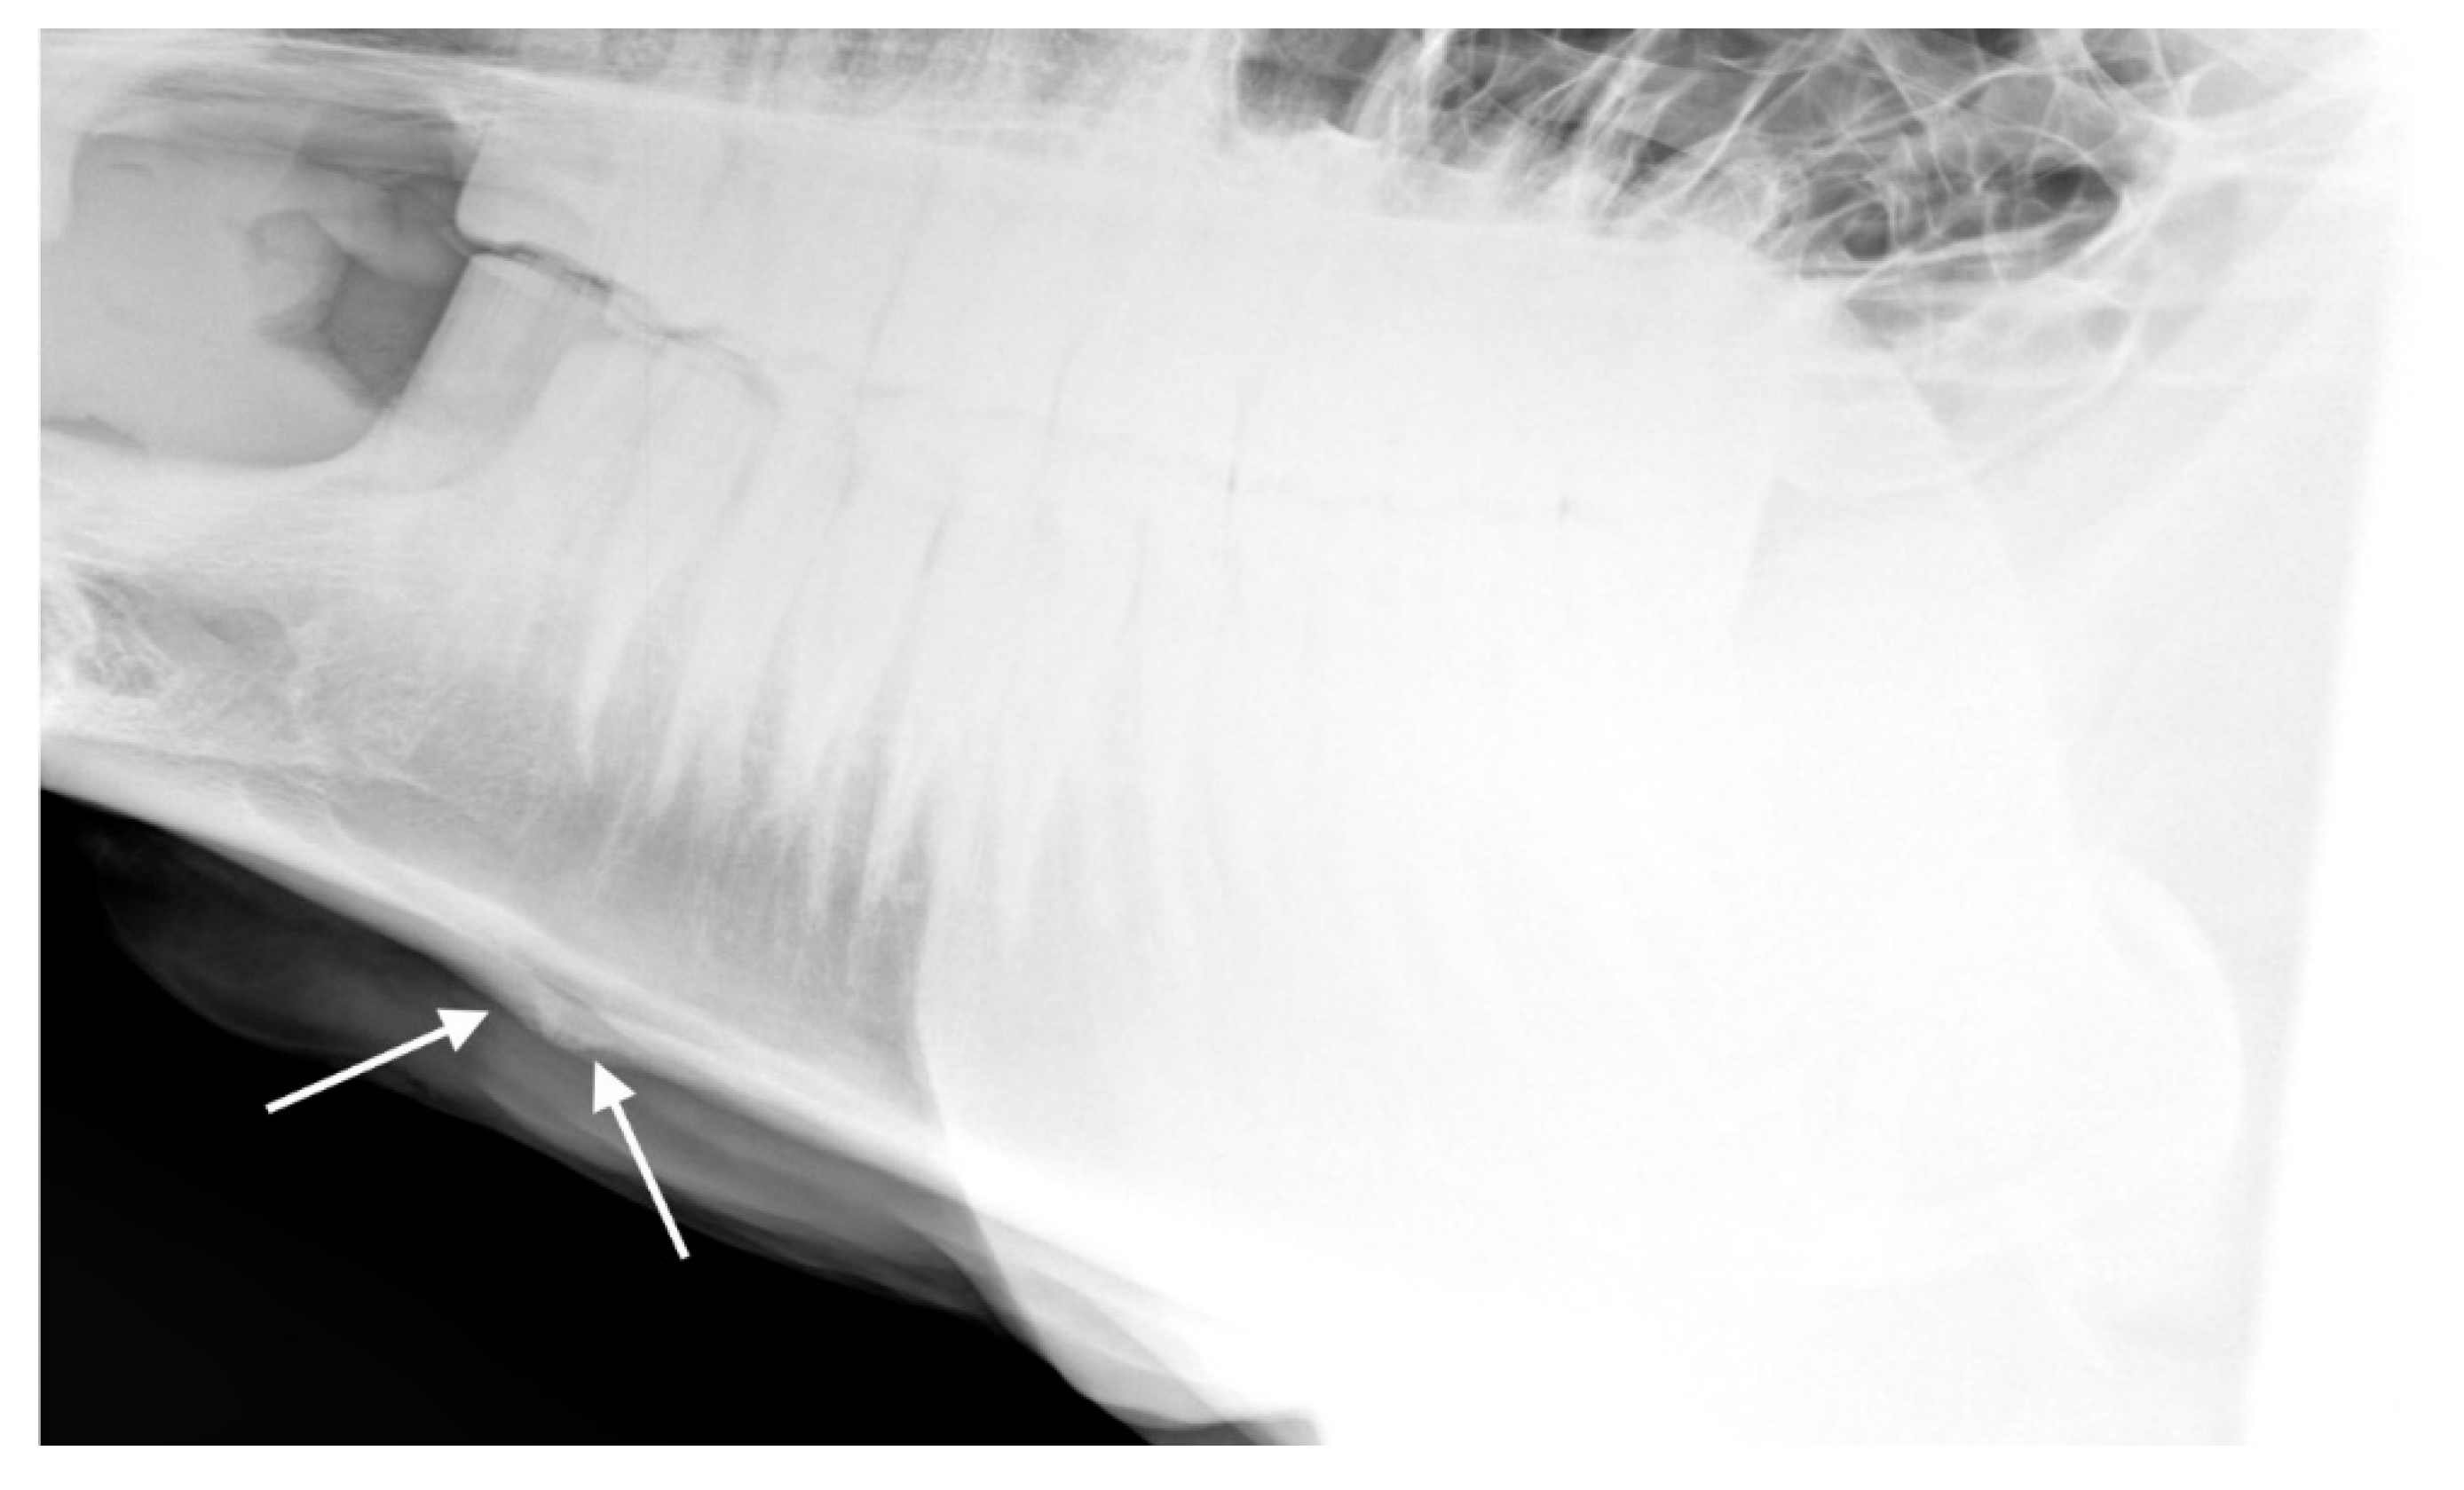

For the 32 horses where the radiologists agreed there was at least one radiographic mandible change, the radiologists agreed about the presence or absence of bone deposition in n = 22 (69%; see Figure 8), the presence or absence of loss of bone homogeneity in n = 25 (78%, see Figure 9), the presence or absence of bone thinning in n = 30 (94%), and the presence or absence of soft tissue swelling in n = 18 (56%). An example of a radiograph showing both bone thinning and bone deposition is shown in Figure 10.

Figure 8. Radiograph showing the mandible of a horse in which radiologists (n = 2) agreed there was bone deposition that was: (a) typical of affected horses and (b) moderate.